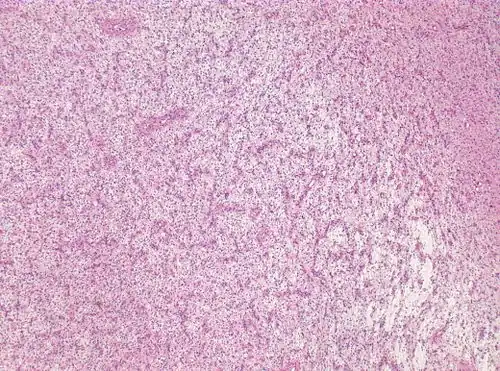

For further confirmation, the clinicians require biopsy and immunohistochemical staining of the resected tumor after surgery. The infiltrative AG cells display positive results for several immunostainings, especially the glial fibrillary acidic protein (GFAP) and epithelial membrane antigen (EMA).[1] Clinicians also observe a specific dot-like pattern from the stained EMA photomicrograph.[3] Other specific AG immunohistochemical tests include Ki-67 proliferative marker, neurospecific nucleoprotein (NeuN), protein 53, synaptophysin (Syn), oligodendrocyte transcription factor-2 (Olig-2) and creatine kinase (CK).[3] In the 2016 WHO classification of CNS tumors, AG is characterised as GFAP-positive, NeuN-positive and low Ki-67 proliferative rate with a perivascular growth pattern.[13]